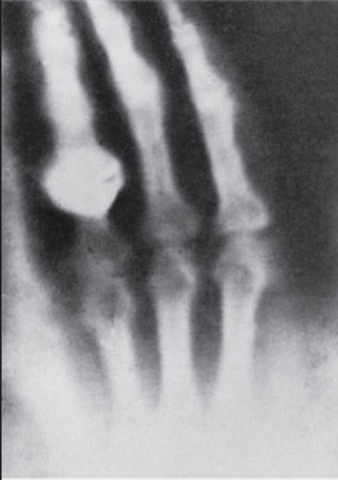

• La primera exploración de rayos X en los Estados Unidos

La primera exploración de rayos X en los Estados Unidos

A principios de febrero de 1896 en el laboratorio de física de Dartmouth College, el profesor E.B. Frost y el Dr. G.D Frost llevaron a cabo ‘la primera exploración de rayos X en los Estados Unidos’. La maquina de ‘la luz X’ fue instalada por el profesor F.G. Austin. La exploración se realizo con un joven con la muñeca fracturada -con su consentimiento- fue utilizado para producir la fotografía por ‘la luz X’.